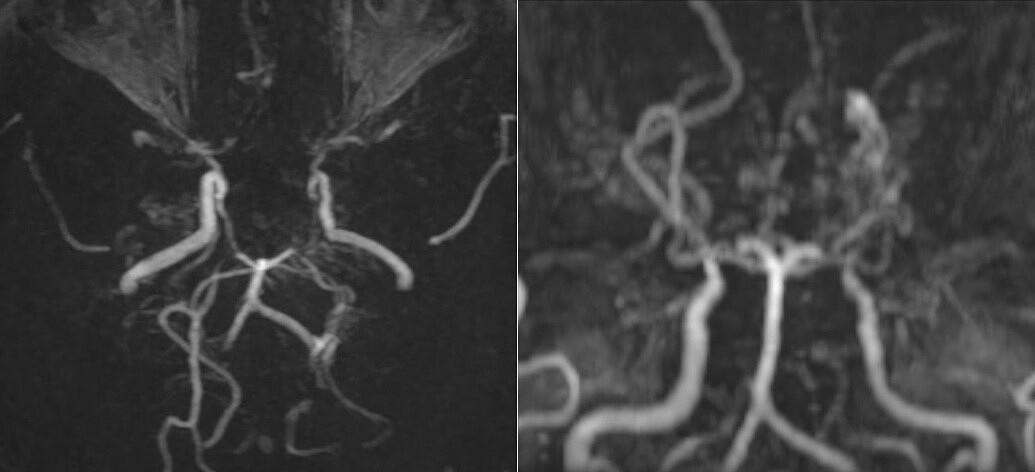

Kết quả khám lâm sàng nhận thấy người bệnh không có dấu hiệu thần kinh khu trú hay tăng áp lực nội sọ. Khi chụp cộng hưởng từ (MRI) sọ não, bác sĩ phát hiện hình ảnh tổn thương hẹp tắc động mạch cảnh trong hai bên và các nhánh, xung quanh có nhiều mạch máu nhỏ bất thường. Trên phim chụp mạch não, các mạch này tạo thành đám, tỏa mờ như “làn khói thuốc lá” – dấu hiệu đặc trưng của bệnh Moyamoya.

Các mạch máu não của bệnh nhân nhìn như “làn khói thuốc lá” trên phim chụp MRI. Ảnh: Bệnh viện cung cấp

Bác sĩ Phạm Thị Yến, chuyên khoa Chẩn đoán hình ảnh, cho biết Moyamoya là một rối loạn mạch máu tiến triển, trong đó động mạch cảnh trong hộp sọ bị tắc nghẽn hoặc thu hẹp, làm giảm lưu lượng máu đến não. Điều này có thể dẫn đến hậu quả như vỡ động mạch và xuất huyết trong sọ. Các mạch máu nhỏ sau đó mở ra ở đáy não trong nỗ lực cung cấp máu cho não. Những cụm mạch máu nhỏ này không thể cung cấp máu và oxy cần thiết cho não, dẫn đến chấn thương não tạm thời hoặc vĩnh viễn.

Tên gọi của bệnh xuất phát từ ca bệnh lần đầu được phát hiện tại Nhật Bản. Moyamoya trong tiếng Nhật Bản là “làn khói thuốc lá”, mô tả những mạch máu nhỏ bất thường, trông giống như làn khói thuốc.